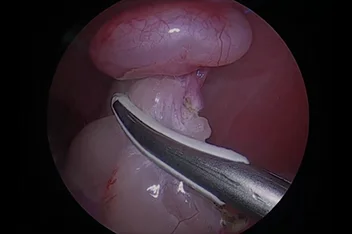

관절경

개,고양이 들은 다양한 관절질환이 존재하고, 복합적으로 존재하는 경우도 빈번합니다.

정확한 진단이 나지 않은 뒤 수술을 하게되면 증상개선이 더디거나 개선이 안될 수 있어, 정확한 진단이 필요합니다.

관절의 경우 X-ray 촬영등으로 진단의 한계가 명확하며, 상위 검사인 CT, MRI 촬영으로도 진단의 한계가 있습니다.

이때 관절경은 내부 구조물들을 직접 시각화 하여 보다 정확한 관절의 상태를 확인하고 진단할 수 있으며, 진단과 치료를 동시에 진행하는 경우도 있습니다. 대표적으로 십자인대단열(CCLR), 골연골염(OCD), 자뼈꿈치돌치유합부전(UAP), 내측관상돌기질환(MCD) 등에 활용될 수있습니다.

관절경 팔꿈치관절(Elbow) 확인

관절경 무릎관절(Stifle) 확인 (반월판 및 십자인대)

* 리본동물의료센터 케이스 사진으로 무단 복제 및 도용을 금지합니다.